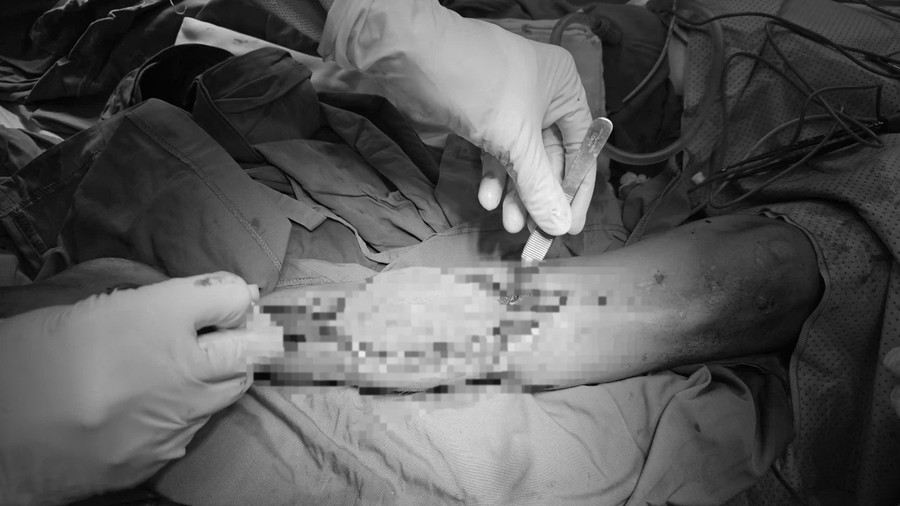

Bệnh nhân được phẫu thuật cắt bỏ đoạn xương viêm, làm mới ổ gãy, chuyển phức hợp vạt da xương mác tự do từ chân đối diện. (Ảnh: BVCC)

Sau khi thăm khám và hội chẩn, bệnh nhân L. được chẩn đoán khuyết xương chày cẳng chân trái sau viêm xương tủy xương mạn tính. Ekip phẫu thuật tiến hành cắt bỏ đoạn xương viêm, làm mới ổ gãy và chuyển phức hợp vạt da – cân – cơ – xương mác tự thân từ chân đối diện, nối vào bó mạch chày trước cẳng chân trái bằng kỹ thuật vi phẫu, kết hợp xương bằng nẹp vis.

BS.CKII Thân Văn Hùng, Phó Trưởng khoa Bỏng – Tạo hình, Viện Chấn thương Chỉnh hình, cho biết, ca mổ có hai kíp song song thực hiện ở chân cho và chân nhận. Một kíp lấy phức hợp vạt da - cân - cơ - xương mác tự thân từ chân đối diện, kíp còn lại bộc lộ mạch máu tại vị trí khuyết xương chày trái dài khoảng 8 cm. Sau đó, phần vạt được chuyển sang nối mạch tại vùng nhận bằng kỹ thuật vi phẫu.